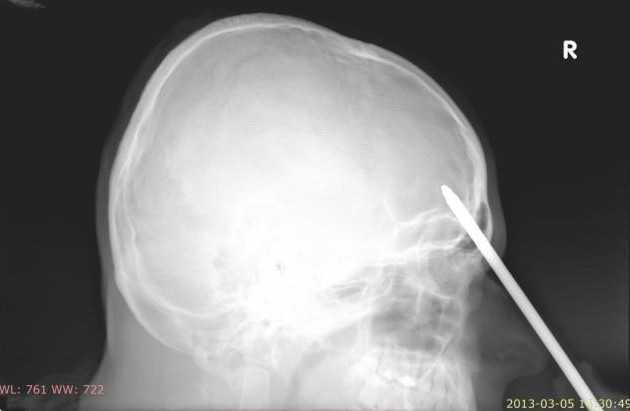

Bị tua vít đâm xuyên đầu vẫn bình tĩnh hút thuốc

(VTC News) - Ngay sau khi phát hiện ra sự thật đáng sợ đó, nạn nhân vẫn tỏ ra bình tĩnh và tiếp tục mồi thuốc hút trước khi nhờ hàng xóm chở đến bệnh viện.